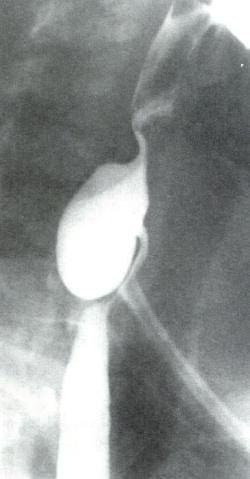

食管X线吞钡

为诊断Zenker憩室的首选检查(图2.6)。

Zenker憩室的X线表现

图2.6Zenker憩室的X线表现。憩室囊位于食管后方。